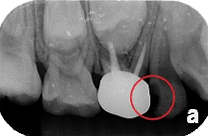

根尖 X 光片(Periapical X-rays)

顯示出整個牙齒、牙冠、牙根尖及牙齒周圍的骨骼組織,可以用來評估牙齒蛀牙的範圍與深度。